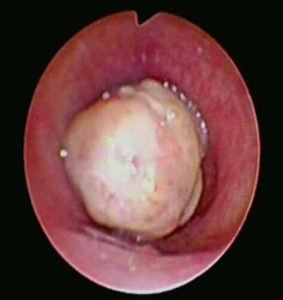

Contrast enhanced computed tomography (CECT) of neck and thorax reported intraluminal mildly enhancing polypoidal mass lesion measuring 2.58 x 1.54 x 1.51 cm (Cc X AP X Tr) in the upper trachea at the level of C6, C7 vertebral body. Significant luminal compromise was noted at the level of the mass lesion. Rest of the lung parenchyma was unremarkable. Flexible bronchoscopy examination revealed a large polyploidal growth approximately 3 cm from the vocal cords. The growth was moving with respiration and causing critical airway narrowing at the upper trachea (approximately 80%).

Diagnostic Flexible bronchoscopy Examination